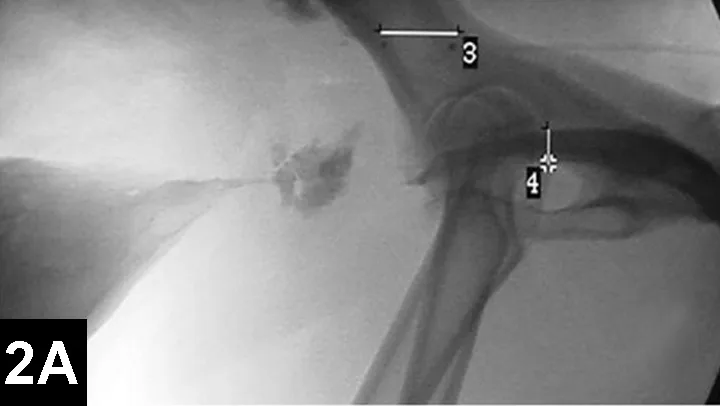

IR techniques that involve placement of an intraluminal stent to alleviate signs associated with malignant obstructions have been described in veterinary patients (Figure 2).5 The author has performed multiple palliative stenting procedures in the urinary tract and upper and lower GI tracts and has relieved luminal obstructions caused by neoplasia or intractable benign strictures in many different sizes of animals, including ferrets.5-11 The IR techniques were fast, safe, and effective. Complications were minor and uncommon.

Figure 2A: Serial lateral positive contrast urethrocystograms in a dog with a malignant urethral obstruction secondary to a prostatic tumor.

Maximal urethral diameters measured using a colonic marker catheter to adjust for radiographic magnification.